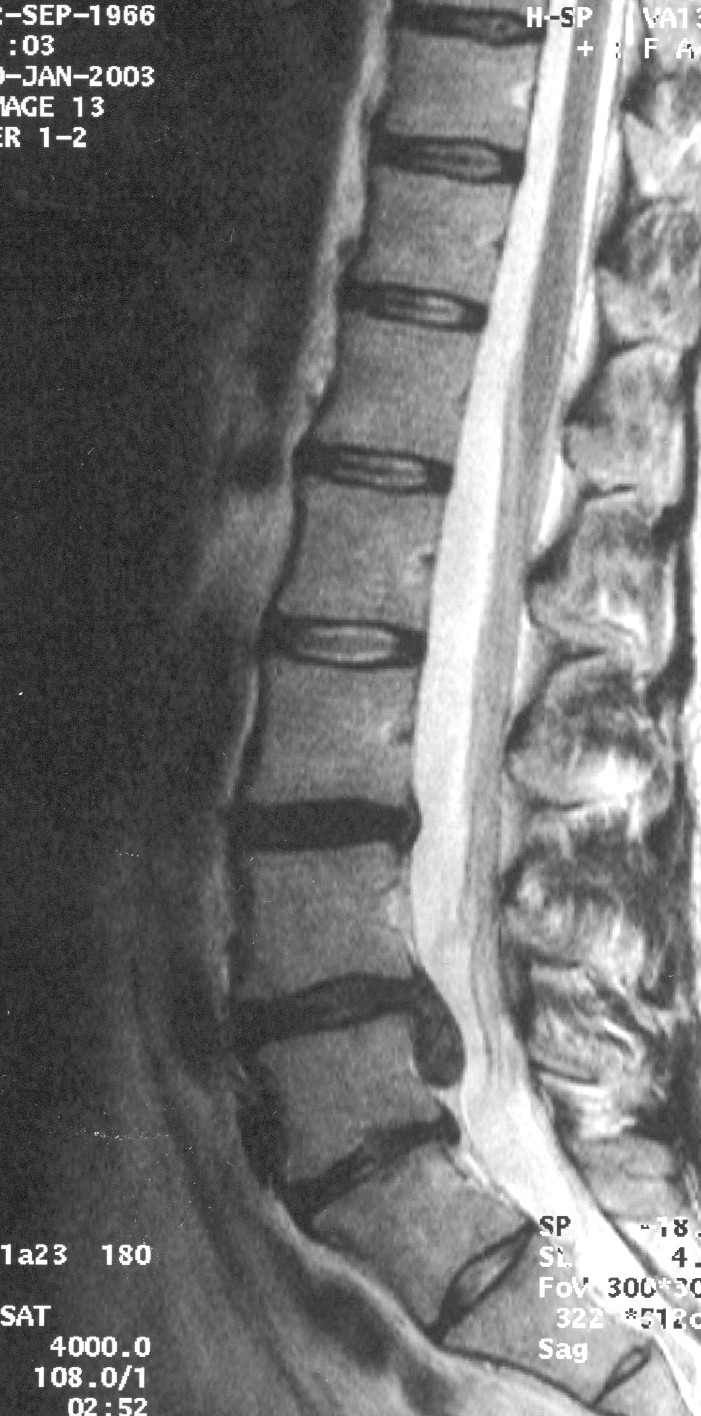

Als Vorgeschmack einige Bilder zum zukünftigen Inhalt: